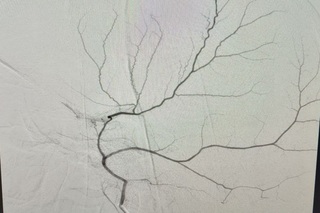

Хроническая субдуральная гематома — это инкапсулированное кровоизлияние под твердой мозговой оболочкой, которое, постепенно увеличиваясь в объеме, сдавливает головной мозг. Её рост часто обусловлен поступлением жидкости через богатую сосудистую сеть, формирующуюся в капсуле гематомы и питаемую средней оболочечной артерией. Суть новой эндоваскулярной методики заключается в прицельной закупорке этой артерии, что прекращает питание капсулы гематомы и способствует её постепенному регрессу (рассасыванию), не влияя на кровоснабжение головного мозга. Данный подход радикально снижает риски осложнений и повторных гематом.

После детального обследования хирург Александр Майоров предложил применить новую тактику. Уже через четверо суток контрольная СКТ показала значительный регресс гематомы (не менее 20%) и уменьшение смещения мозга с 4 мм до 2 мм.